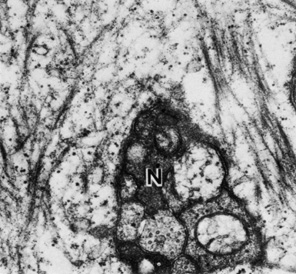

The corneal epithelium is the anterior-most cell layer of the cornea (Fig. 1). It is typically several cell layers thick, consisting of the apical cell squamous layer, the multilayered, polygonal-shaped wing cells beneath the apical layer, and the posterior-most layer of basal cells (Fig. 2). The wing cell layer is two or three cells thick in the central cornea, but tends to be four to five cells thick in the periphery. In total, the epithelium is approximately 50 μm thick in the central human cornea.

Fig. 2. Full-thickness electron micrograph of corneal epithelium. Note the cell shape change with depth, the variation of cell membrane interdigitation, and the intracellular differences between cell types. S, apical surface cells; W, wing cells; and B, basal cells. Also note the microvilli seen along the apical membrane of the surface cells (3,620×). Inset: Epithelium (E) overlies a thin, dense basement membrane (arrow) with no discernible laminar appearance (periodic acid-Schiff [PAS] stain, 330×). (Courtesy of Drs. Rodrigues, Waring, Hackett, and Donohoo.)